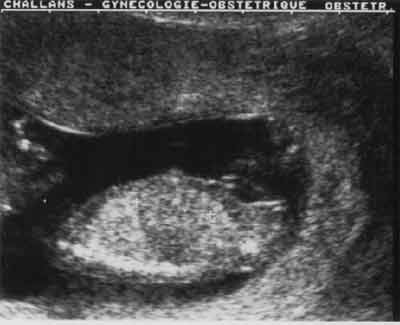

Foie : coupe para-sagittale